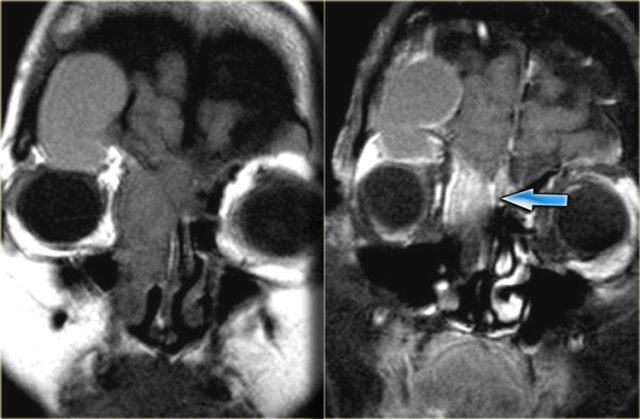

Coronal images of the same patient: T1 pre-and post-contrast.

Normal aspect of the right Meckel's cave, tissue in the left Meckel's cave extending into the cavernous sinus (blue arrow).

The red arrow points to the dural margin of the cavernous sinus: there is enhancement on both sides of the dura.

The disease wraps around the temporal lobe (green arrow) and extents downward in the foramen ovale (yellow arrow) and into the masticator space.

The asterix indicates normal non-enhancing tissue in the masticator space.

This patient had a lymphoma.

Nine out of ten times an immunocompromised patient will have a fungal infection, in one out of ten it will be a lymphoma.

CT and MR have a complimentary role in this case, but finally a biopsy is called for to differentiate between these two diagnoses, because of different treatment.